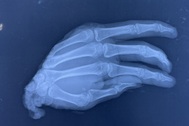

Trước đó, tối 19/6, nam thanh niên tên N.T.Đ. (32 tuổi, quê Đồng Nai) được chuyển đến một bệnh viện tại TPHCM cấp cứu trong tình trạng bàn tay bị chém gần lìa, đứt gân, cơ, mạch máu, thần kinh, xương bàn tay đứt, gãy và mất nhiều máu.

Bàn tay chàng trai bị chém gần đứt lìa (Ảnh: Bệnh viện cung cấp).